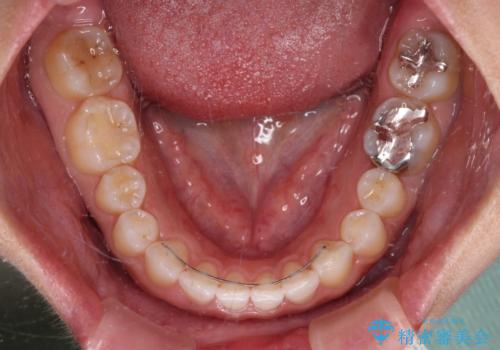

当初は1年程度で終えられると思いましたが、治療途中から装着時間が短くなったり、来院間隔が長期になったりとし、結果として4年半以上の治療期間となりました。

治療途中に上顎前歯は失活してしまいましたが、変色が顕著ではないため、経過を見ていくこととなりました。